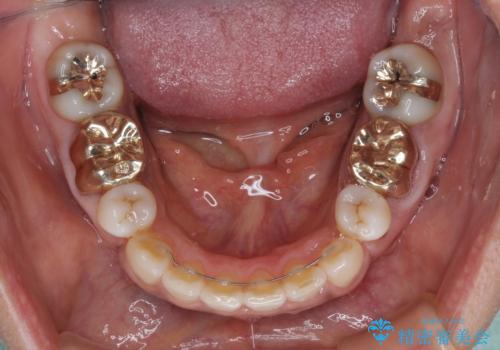

30代女性 色違いの前歯をセラミックできれいに

- 10年以上前に被せた前歯のクラウンと、レジンにより虫歯治療した前歯の色の違いを気にして来院された患者様です。

2歯をオールセラミッククラウン(ジルコニアクラウン)にて補綴することとしました。

10年以上もの間、前歯の色の違いに悩んでいらっしゃったようですが、歯茎のラインの黒ずみが見えたことをきっかけに治療を決意されました。

わずか1ヶ月半の間にまるで自分の歯のようなセラミッククラウンが装着され、患者様には大変満足していただきました。